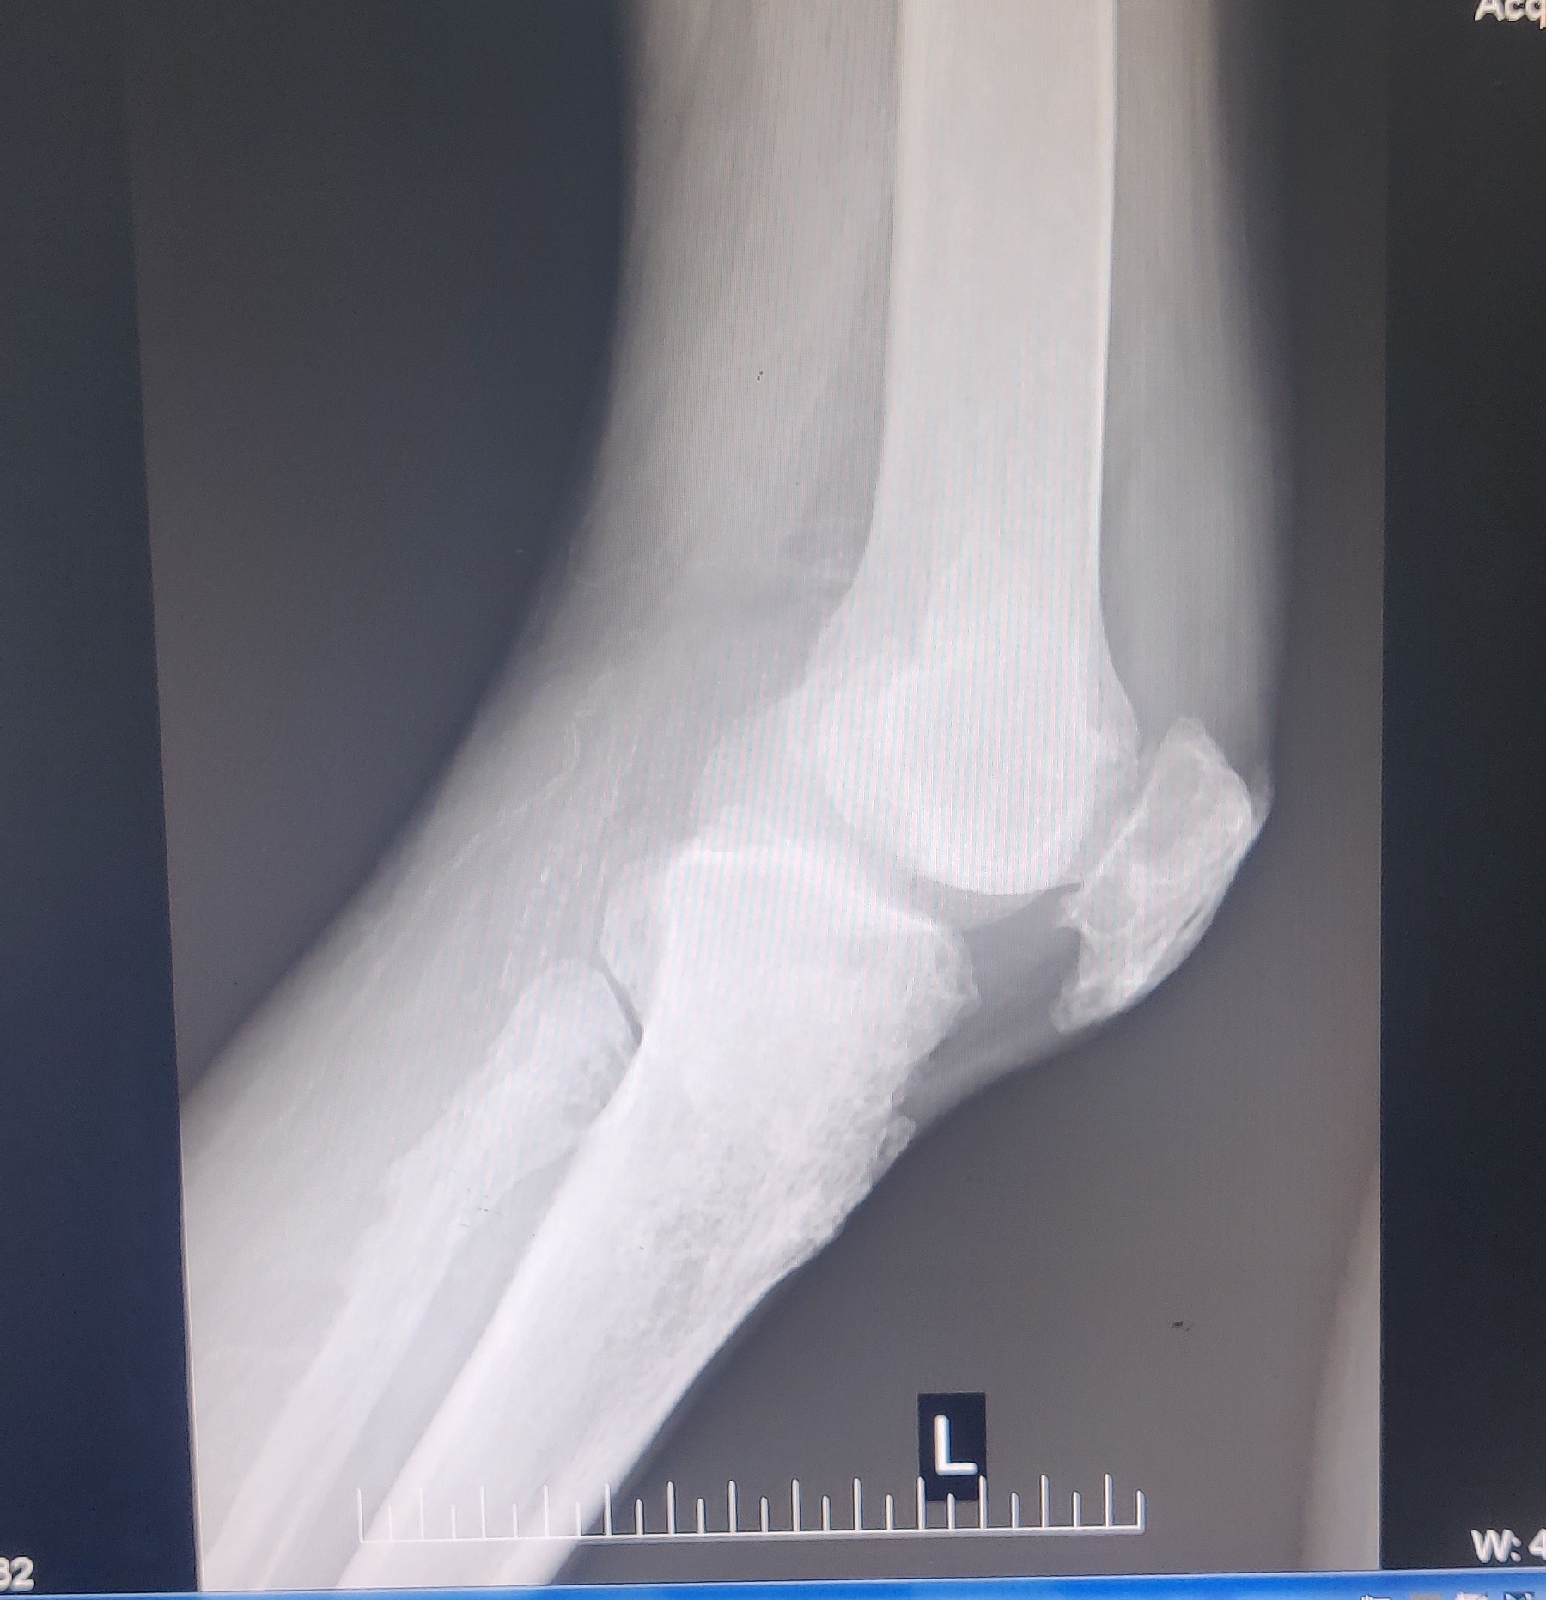

C/o On and off of Joint pains in hips, knee, ankle, wrists, elbow, fingers, One joint at a time.

Pain initially starts in the wrists,swelling appears ( flexion occurs at metacarpal- phalanges joint )for 1 to 2 days and pain migrates to elbow (unable to flex completely, swelling +) for 2 days and then pain migrates to shoulder (unable to lift ,abduct the shoulder )and then other hand involves.

Pain initially get started in the ankle (swelling+, duration 1-2 days and pain migrate to Knee (unable to bear weight, walk with help of stick/support, swelling+duration 1-2 days )and then pain migrate to hip joint.